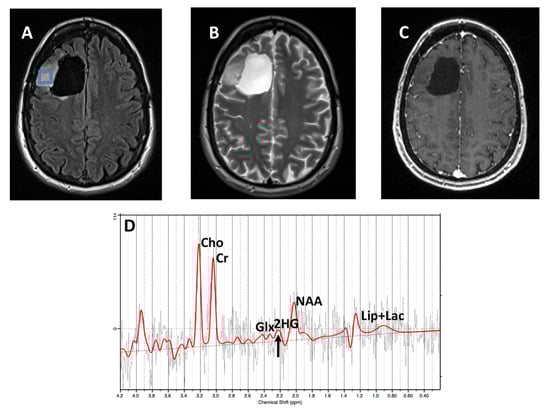

3. Results